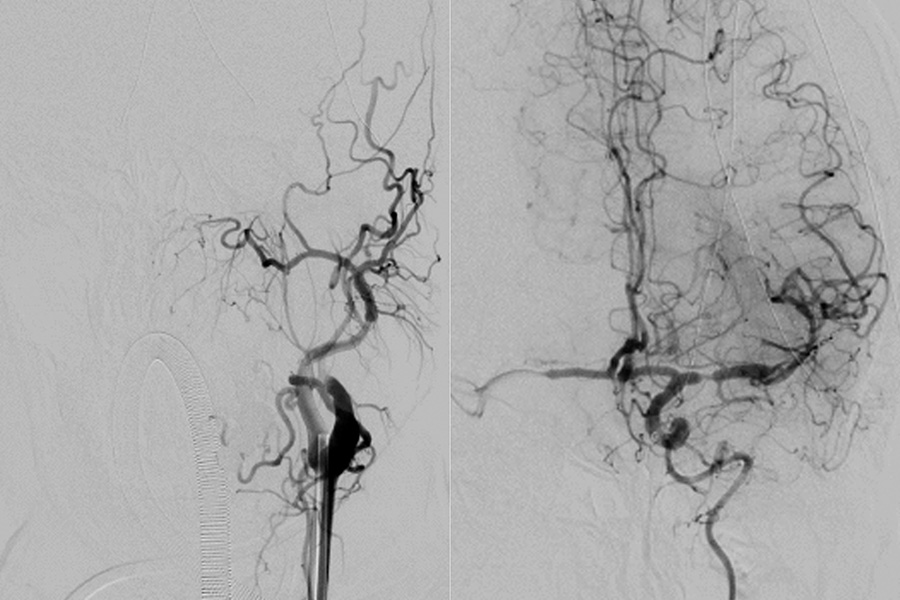

Aufgrund der plötzlichen klinischen Verschlechterung am späten Abend wurde in der Klinik Favoriten akut eine Computertomographie (CT) durchgeführt. Zu dem Zeitpunkt war die Patientin bereits so unruhig, dass eine Narkose eingeleitet werden musste, um die Untersuchung durchführen zu können. Die Untersuchung zeigte, dass durch den Riss in der Halsschlagader ein Blutgerinnsel entstanden war, das in weiterer Folge mit dem Blutstrom ins Gehirn gelangt war und dort einen Gefäßverschluss verursacht hatte. Daraufhin wurde die Patientin mitten in der Nacht von der Klinik Favoriten in die Klinik Landstraße gebracht. In der Klinik Landstraße befindet sich neben der Stroke Unit – der Spezial-Station für Schlaganfall-Patient*innen – auch eines von drei Zentren für zerebrale Thrombektomien in Wien. In diesen Zentren eröffnen interventionelle Radiolog*innen akute Gefäß-Verschlüsse des Gehirns minimalinvasiv, also ohne große Operation. Nach dem Eintreffen in der Klinik Landstraße wurde bei Frau K. aufgrund des protrahierten undulierenden Verlaufs zuerst noch eine spezielle CT-Untersuchung durchgeführt, die eine bessere Beurteilung der Durchblutung des Gehirns erlaubt. Diese CT-Perfusion zeigte, dass ein großer Teil der linken Gehirnhälfte nicht mehr durchblutet ist. In dieser Nacht ist Oberarzt Joachim Vavrik im Dienst, ein sehr erfahrener interventioneller Radiologe. Aufgrund der heiklen Situation verständigt dieser Rüdiger Schernthaner, den Vorstand des Radiologie-Instituts. Primar Schernthaner begutachtet daheim kurz die Bildgebung und fährt dann nach erneuter Rücksprache mit Oberarzt Vavrik sofort in die Klinik Landstraße. Mit einer Angiographie des Gehirns – dabei können Gefäße sichtbar gemacht werden – können die beiden interventionellen Radiologen die Lage der Gefäßverschlüsse in der Halsschlagader und im Gehirn exakt bestimmen. Mit einem speziellen Draht und einem Katheter (ganz dünner Plastikschlauch) sondieren die beiden, von der Leistenarterie kommend, durch das verschlossene Halsgefäß bis zu dem Verschluss im Gehirn. Mit einem sogenannten Stent-Retriever (ein Metallgeflecht) können sie dann das Blutgerinnsel mobilisieren und entfernen. Der Erfolg ist sofort sichtbar: Die linke Hirnhälfte von Frau K. wird wieder durchblutet. „So ein Eingriff ist immer mit einem Risiko verbunden. Wenn wir ein Gefäß verletzen, kann dies eine Gehirnblutung auslösen. Bei diesen Einrissen der Halsschlagader gelingt es manchmal nicht, das Gefäß wieder zu eröffnen. Dennoch war der Eingriff, auch im Hinblick auf das niedrige Alter der Patientin, alternativlos“, erzählt der Institutsvorstand. Bei Frau K. läuft alles gut.